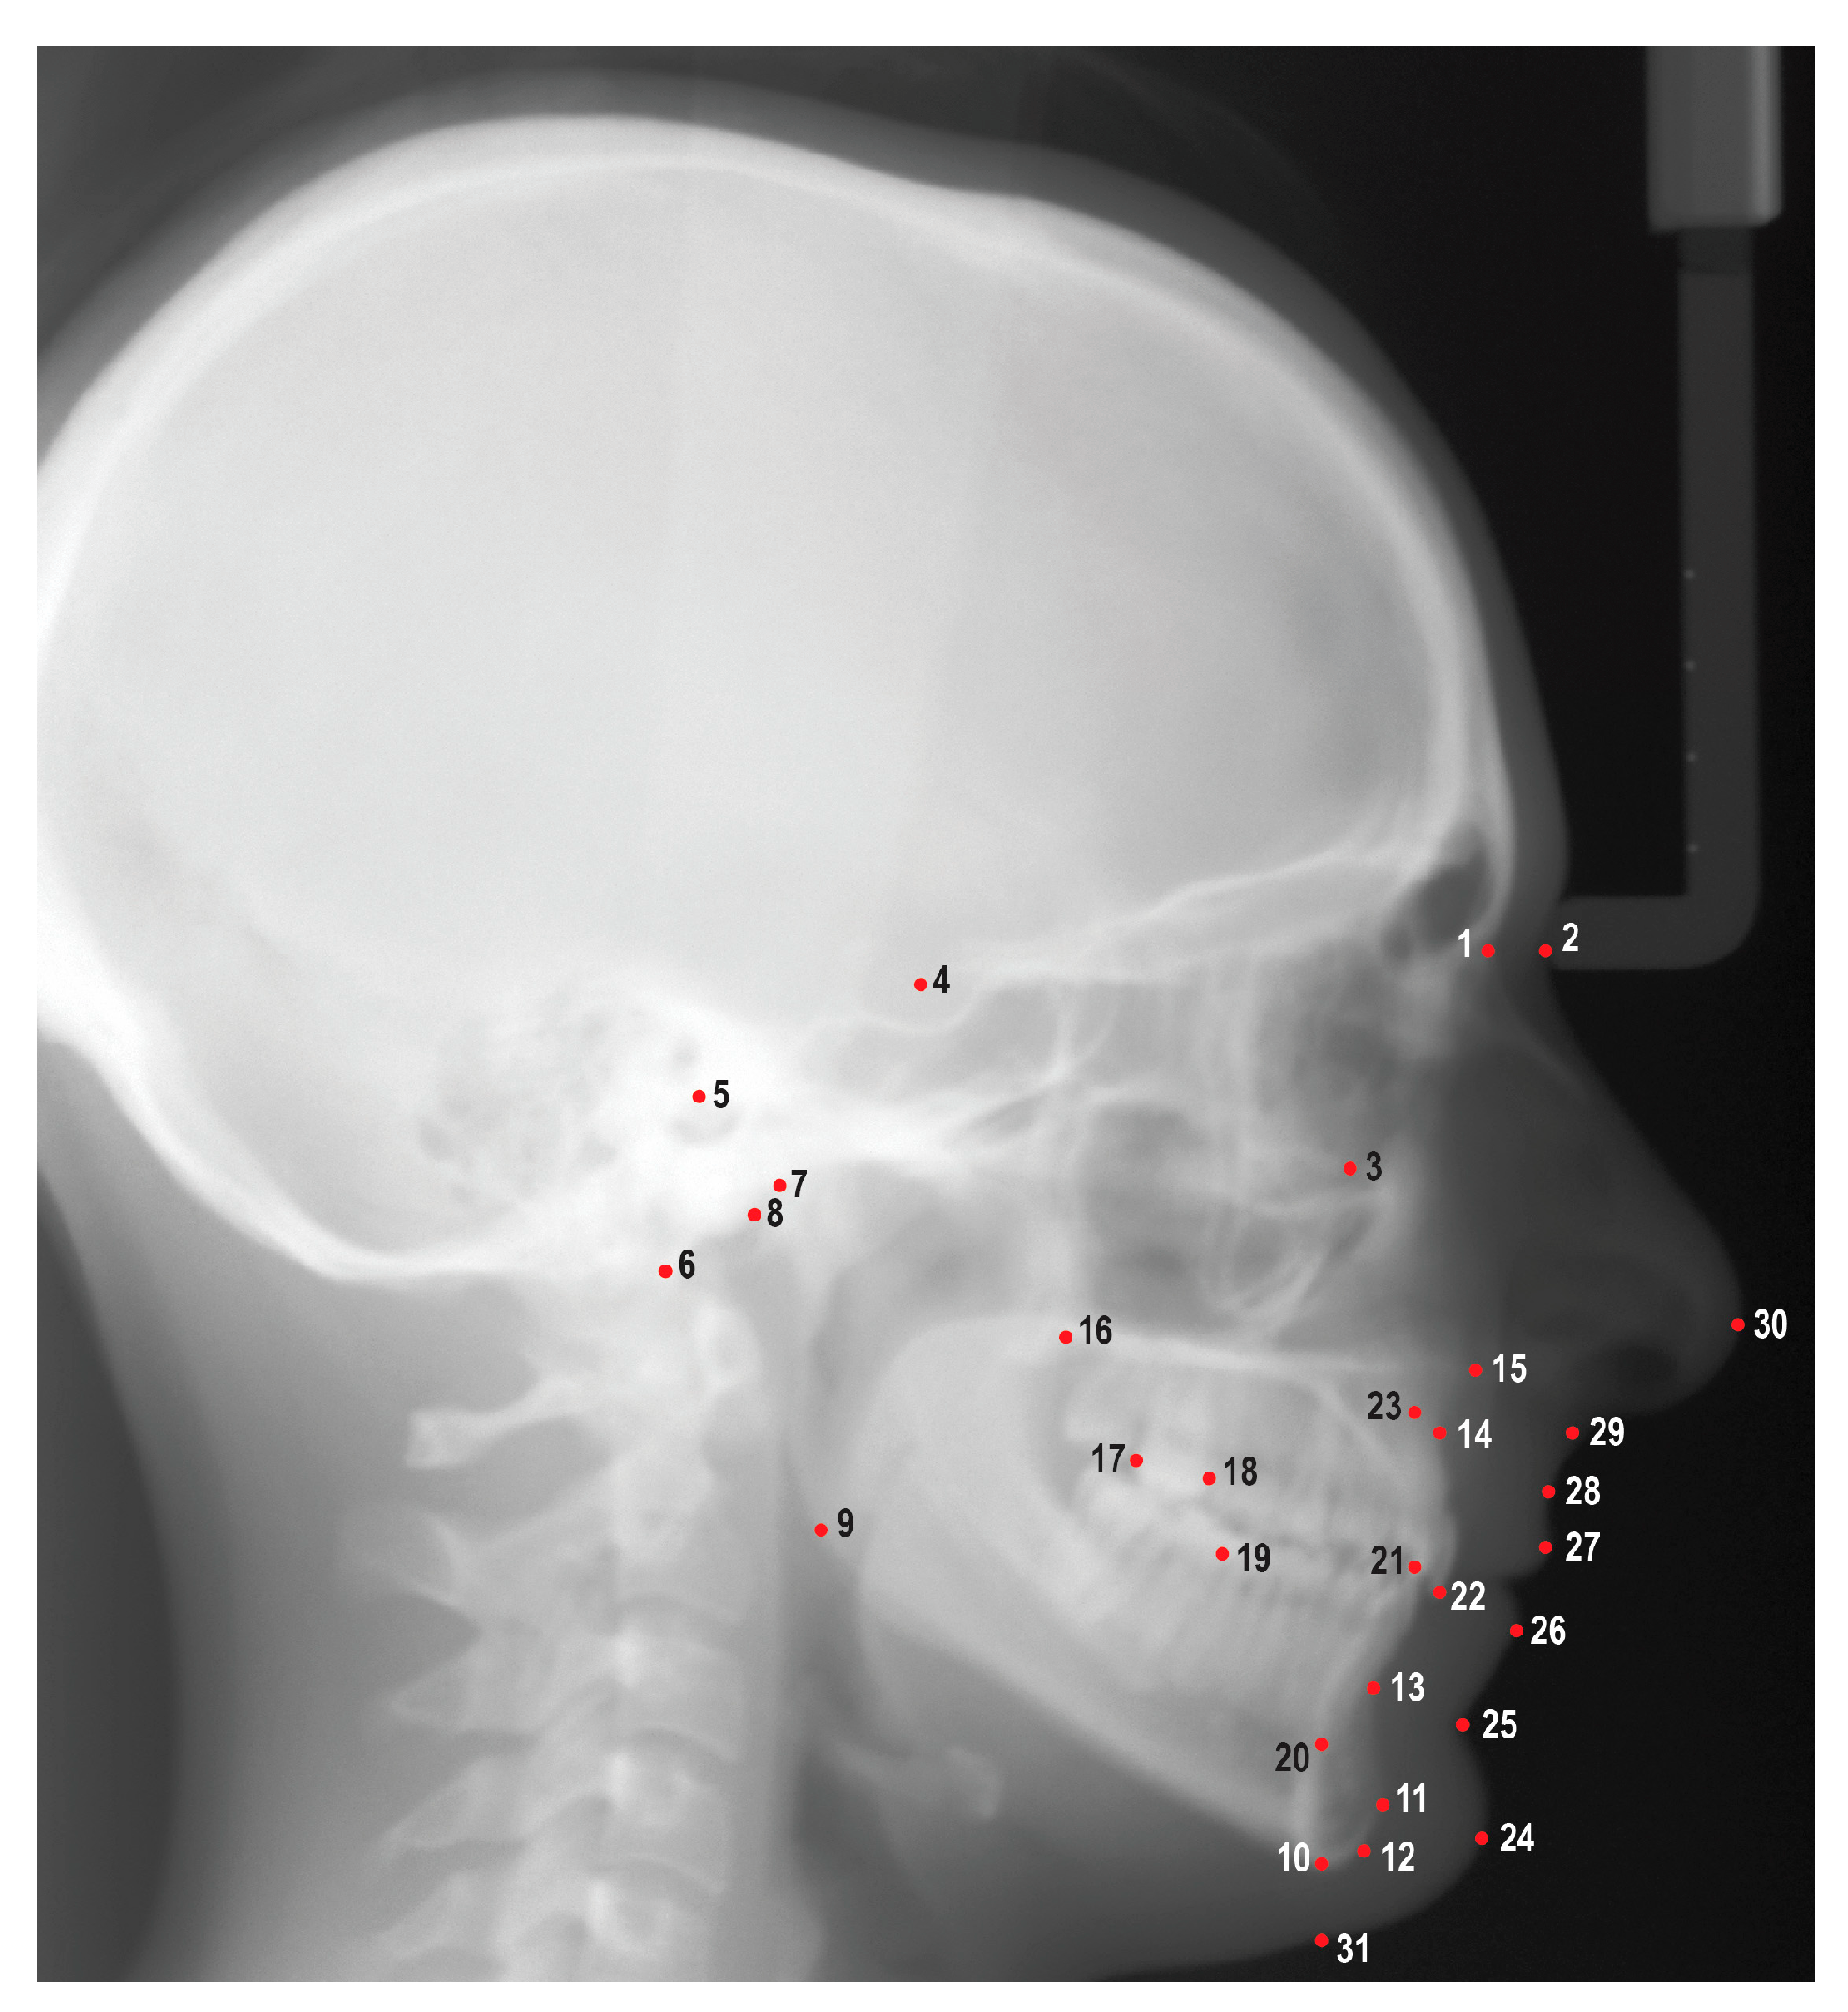

An experienced orthodontic faculty member (HT) and three orthodontic residents (JV, TM, LL) attended three calibration sessions prior to reviewing and tracing the cephalometric radiographs. A total of 31 cephalometric landmarks were identified using Dolphin Imaging Software (Patterson Dental, Saint Paul, MN) (Figure 1). These cephalometric landmarks were used to generate a cephalometric analysis that included 46 linear and angular measurements (Table 1). Demographic and treatment information including age, gender, race, ethnicity, actual treatment time, additional appliances, and COVID factor were gathered from the IUSD electronic practice management software (Axium, Exan Software, Las Vegas, NV). Additional appliances factor included impacted canines, expanders, and headgear. COVID factor was included if patient was being treated during the pandemic when IUSD limited elective dental appointments (March 2020 – June 2020). Maxillary/mandibular TSALD and molar classifications were collected by utilizing pretreatment photographs and digital casts. TSALD was categorized into no crowding/spacing (<1mm), mild crowding/spacing (1-3mm), moderate crowding/spacing (4-7mm), and severe crowding/spacing (>8mm).

Figure 1. Cephalometric landmarks used in this study. 1: Nasion (N), 2: Soft tissue nasion (N’), 3: Orbitale (Or), 4: Sella (S), 5: Porion (Po), 6: Basion (Ba), 7: Condylion (Co), 8: Articulare (Ar), 9: Gonion (Go), 10: Menton (Me), 11: Pogonion (Pog), 12: Gnathion (Gn), 13: B point (B), 14: A point (A), 15: Anterior nasal spine (ANS), 16: Posterior nasal spine (PNS), 17: Distal of upper first molar (U6d), 18: Mesial of upper first molar (U6m), 19: Mesial of lower first molar (L6m), 20: Lower incisor root apex (L1a), 21: Lower incisor incisal edge (L1i), 22: Upper incisor incisal edge (U1i), 23: Upper incisor root apex (U1a), 24: Soft tissue pogonion (Pog’), 25: Soft tissue B point (B’), 26: Lower lip (Li), 27: Upper lip (Ls), 28: Soft tissue A point (A’), 29: Subnasale (Sn), 30: Pronasale (Pn), 31: Soft tissue menton (Me’).